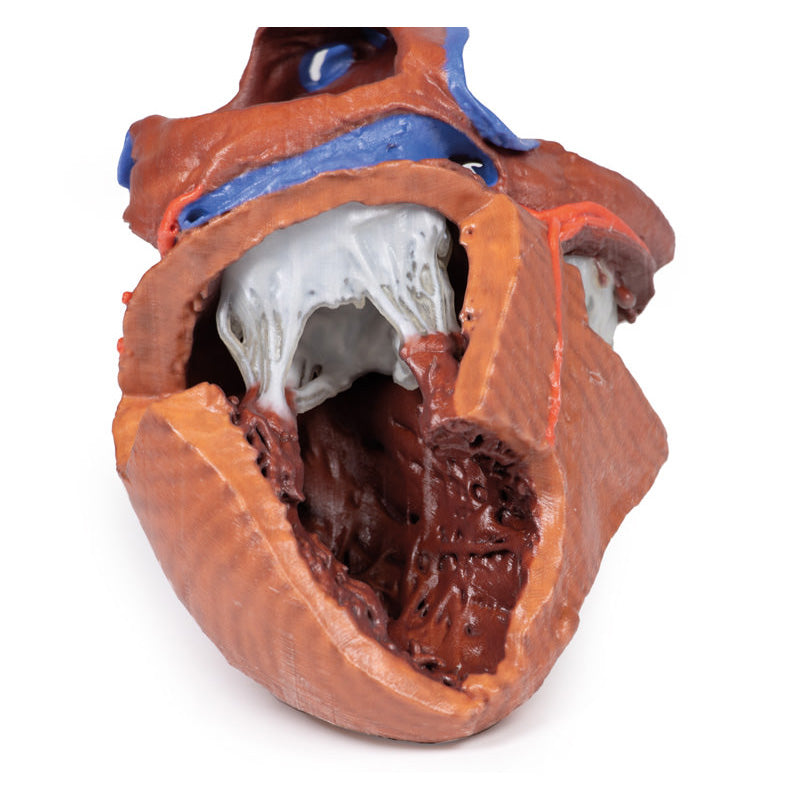

The anterior wall of the right ventricle has also been removed to expose the right atrioventricular valve and its three cusps (anterior, posterior, and septal), including the chordae tendineae connecting them to respective papillary muscles projecting from trabeculae carneae (including a septomarginal trabecula entering the anterior papillary muscle from the interventricular septum). The smooth wall of the conus arteriosus is also exposed leading to the pulmonary semilunar valve (left, right, and anterior cusps) at the base of the pulmonary trunk. Preserved and encircling the right atrioventricular valve is the right coronary artery, ultimately passing to the posterior aspect and the origin of the posterior interventricular artery and atrioventricular nodal artery.

This 3D printed heart has been dissected to display the internal structures of the chambers. At the base of the heart the termination of the superior vena cava is preserved entering the right atrium. Part of the inferior vena cava is also preserved on the inferior aspect of the right atrium; however, most of the vessel lumen and much of the anterior wall has been removed to expose the pectinate muscles of the right auricle and the fossa ovalis (which is nearly translucent in the 3D print).The anterior wall of the right ventricle has also been removed to expose the right atrioventricular valve and its three cusps (anterior, posterior, and septal), including the chordae tendineae connecting them to respective papillary muscles projecting from trabeculae carneae (including a septomarginal trabecula entering the anterior papillary muscle from the interventricular septum). The smooth wall of the conus arteriosus is also exposed leading to the pulmonary semilunar valve (left, right, and anterior cusps) at the base of the pulmonary trunk. Preserved and encircling the right atrioventricular valve is the right coronary artery, ultimately passing to the posterior aspect and the origin of the posterior interventricular artery and atrioventricular nodal artery.